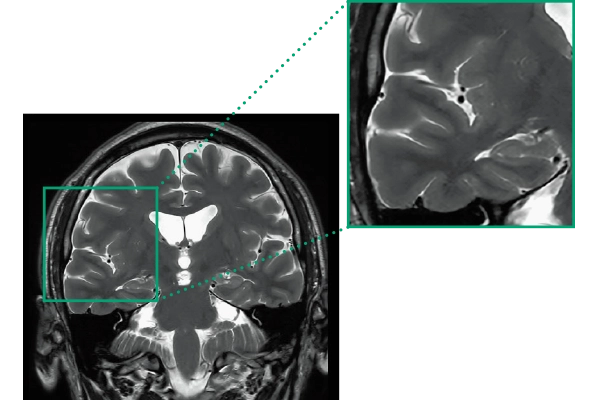

DLR offers 2 options

High Resolution

T2WI, 0.56×0.70×3.0mm, 2:28

ShortScan

FLAIR, 1:14